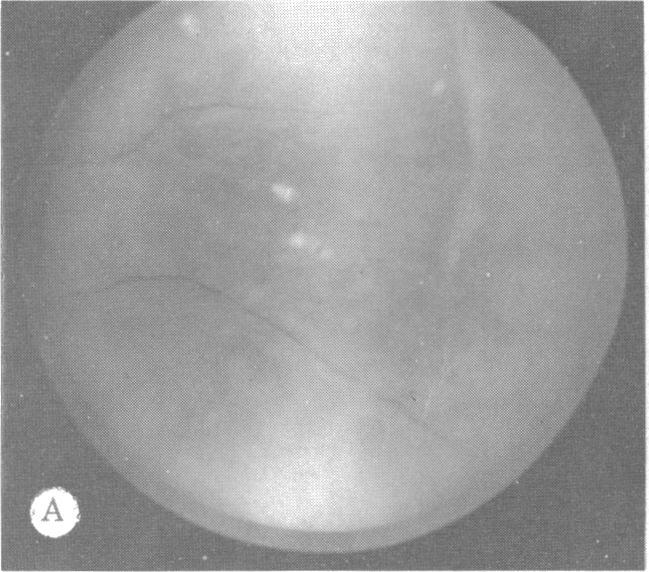

遗传性玻璃体视网膜病变和骨骼发育异常。

Inherited hyaloideoretinopathy and skeletal dysplasia.

Twenty-one patients from five families displaying the ocular defects of dominantly inherited hyaloideoretinopathy as originally described by Wagner were surveyed radiographically for skeletal defects. A mild generalized epiphyseal dysplasia was found in twenty. A comparison of the skeletal dysplasia associated with arthro-ophthalmopathy and that found in families with Wagner's disease reveals more similarities than differences. It is concluded that Wagner's disease is a dominantly inherited syndrome of ocular defects that includes myopia, vitreous syneresis with membranes, and radial perivascular chorioretinal degeneration. It is associated with radiographically demonstrated generalized epiphyseal dysplasia that is manifested clinically by flattening of the mid-face and palatoschisis.

对来自五个家族的21名患者进行了X线检查,以确定是否存在骨骼缺陷。这些患者表现出如Wagner最初所描述的显性遗传性玻璃体视网膜病变的眼部缺陷。在20名患者中发现了轻度全身性骨骺发育异常。对与关节眼病相关的骨骼发育异常和瓦格纳病家族中发现的骨骼发育异常进行比较,结果显示相似之处多于不同之处。得出的结论是,瓦格纳病是一种显性遗传的眼部缺陷综合征,包括近视、伴有膜的玻璃体脱离和放射性血管周围脉络膜视网膜变性。它与X线检查显示的全身性骨骺发育异常有关,临床上表现为中面部扁平及腭裂。